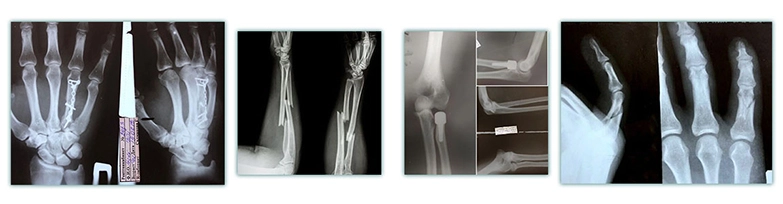

• Лечение кисти, в том числе после травм,

резаных ран, повреждений сухожилий,

а также удаление доброкачественных новообразований

в суставах (в том числе болезненных).

• Хирургическое лечение врожденных

и приобретенных патологий кисти и стопы.

•Артроскопия (минимально инвазивные операции

артроскопом для лечения внутренних частей суставов,

в том числе локтей или коленей).

а также при переломах, в том числе для установки

металлических фиксирующих конструкций или их удаления.

• Лечение кисти, в том числе после травм,

резаных ран, повреждений сухожилий,

а также удаление доброкачественных новообразований

в суставах (в том числе болезненных).

• Хирургическое лечение врожденных

и приобретенных патологий кисти и стопы.

•Артроскопия (минимально инвазивные операции

артроскопом для лечения внутренних частей суставов,

в том числе локтей или коленей).

а также при переломах, в том числе для установки

металлических фиксирующих конструкций или их удаления.